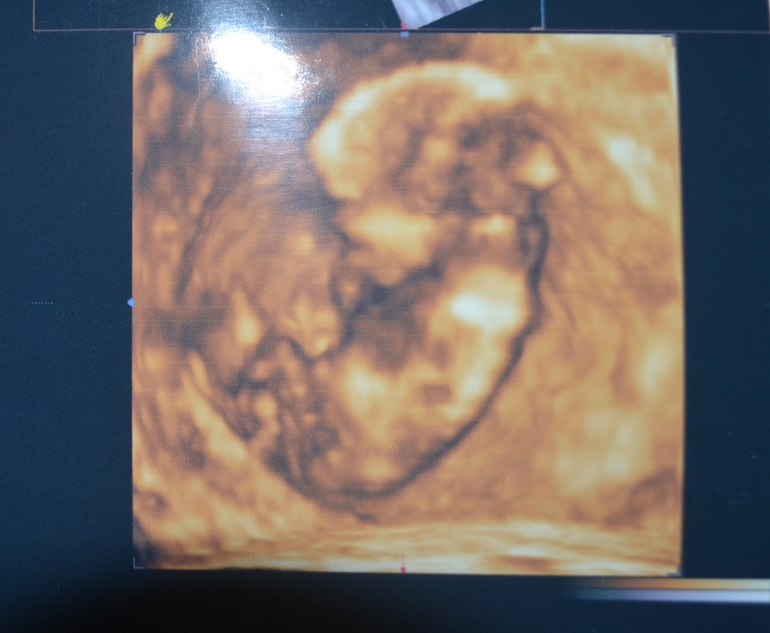

3Д

Уже коллекция почти получилась. Скоро будет третье плановое узи, безумно хочу сделать 3Д фотку, там так личико классно видно, показывали мне качество таких фоток, можно почти сказать на кого похож ребенок, а еще если получится видео хоть чуточку. Но все будет зависеть от малышочка, если будет вредничать и запрячет личико, то придется мне побегать по кабинету